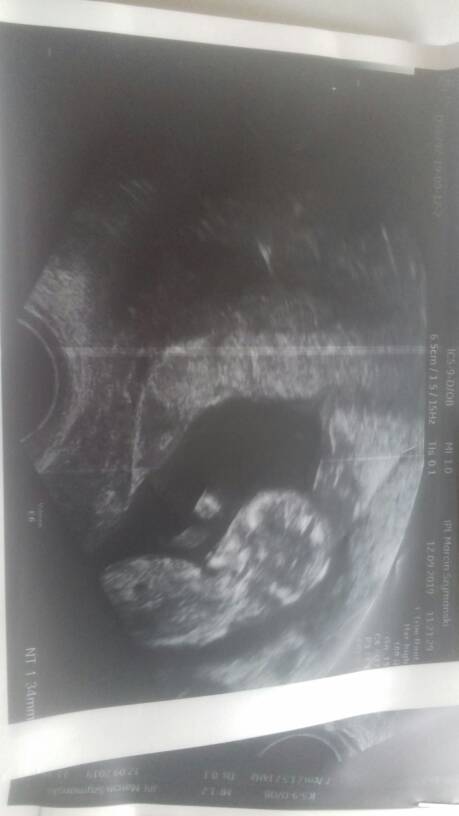

Maluszek ma 47cm 11t3d, serduszko bije 165bpm.

Przeziornosc karkowa 1.34 mm

Kość kosowa 1.27mm

Przeplywy wporzadku.

Nie zalecił żadbych dodatkowych badan gdyż ciąża rozwija sie prawidłowo[emoji5]Zobacz załącznik 1021645Zobacz załącznik 1021646Zobacz załącznik 1021647Zobacz załącznik 1021648